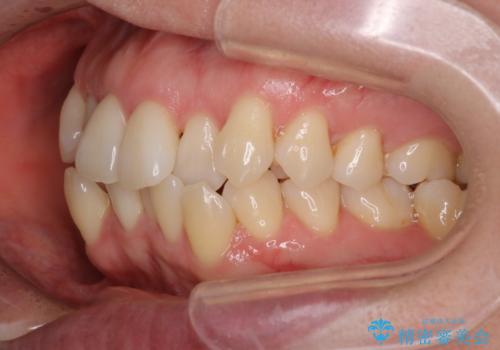

【抜歯ケース】前歯のガタガタをインビザラインで治療

- 前歯のガタガタを主訴に来院されました。

抜歯が必要なケースでしたが、インビザラインでの治療を希望されワイヤーを使用せずに治療を完了しております。